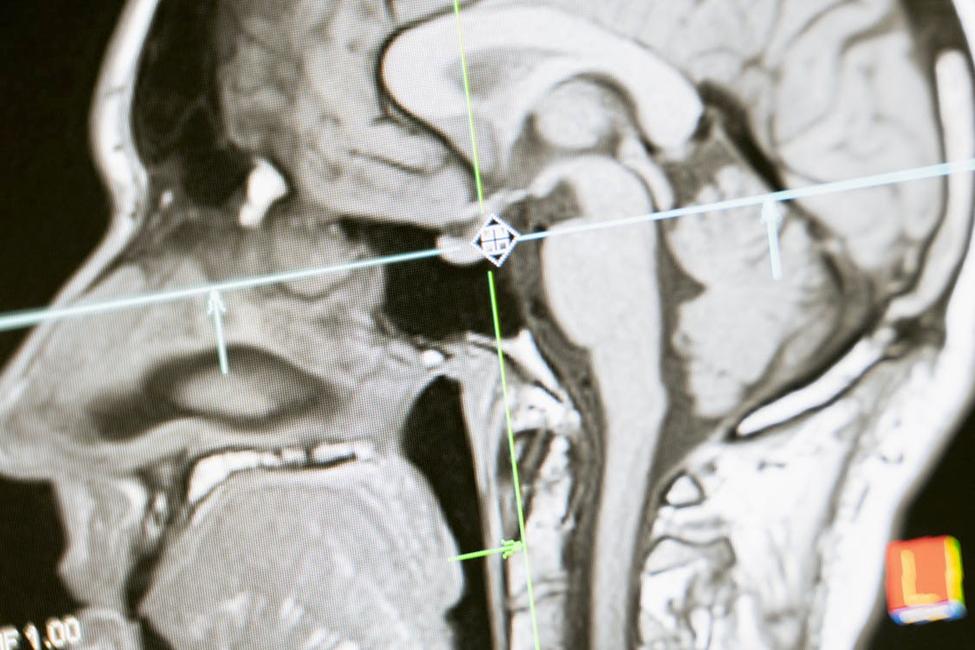

The anterior pituitary gland controls several key hormones that affect growth, energy, reproduction, and stress response. When it produces too much or too little of these hormones, many body systems are affected. Common causes include head injury, stroke, infection, or stress.

Doctors check hormone levels to find where the imbalance starts — in the pituitary, thyroid, or adrenal glands. Treatment may include replacing missing hormones, supporting adrenal function, and improving stress and nutrient balance.